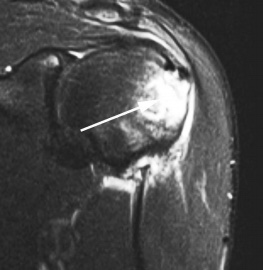

Разрыв вращательной манжеты – также характерное повреждение области плеча – может быть связан как с травмой, так и дегенеративными процессами. Разрывы вращательной манжеты бывают полные и неполные. Кроме того, по МРТ плечевого сустава выделяют 3 градации, в основе которых лежит не только изменение сигнала на Т2-зависимых томограммах, но и морфологические изменения сухожилия.

МРТ. Корональная Т2-зависимая томограмма с подавлением сигнала от жира. Полный разрыв сухожилия надостной мышцы.

При МРТ плечевого сустава косвенным признаком разрыва вращательной манжеты служит высокий сигнал на Т2-взвешенных от поверхности сустава до субакромиальной (субдельтовидной) сумки. Частичные разрывы чаще всего по передней поверхности сухожилия м.supraspinatus, реже примыкая к большой бугристости или сухожилия м. infraspinatus.